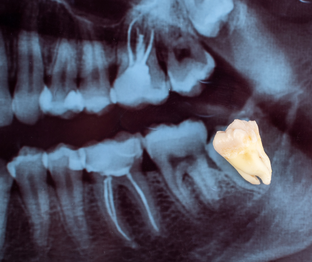

Зубы мудрости — одна из самых спорных тем в стоматологии. Кто-то живёт с ними всю жизнь и не знает проблем, а кто-то сталкивается с воспалениями, болью и сложным лечением уже после 40–50 лет. Поэтому главный вопрос, который задают пациенты: стоит ли лечить зуб мудрости или проще и надёжнее сразу его удалить? Разберём этот вопрос подробно: Почему зубы мудрости часто вызывают проблемы Зубы мудрости прорезываются последними, обычно после 18–25 лет, а у многих — и значительно позже. К этому моменту челюсть уже сформирована, и места для полноценного зуба часто просто не хватает...

Зубы мудрости — пожалуй, самые загадочные в нашем организме. Они появляются последними, когда челюсть уже сформирована, а места для них часто почти нет. У кого-то «восьмёрки» растут без проблем, у других приносят боль, воспаление и требуют удаления. Почему так происходит и когда действительно нужно прощаться с зубом мудрости — рассказывает стоматолог. Зубы мудрости — это третьи моляры, расположенные в самом конце зубного ряда. Обычно они появляются в возрасте от 17 до 25 лет, но у некоторых — позже или вовсе не прорезываются...